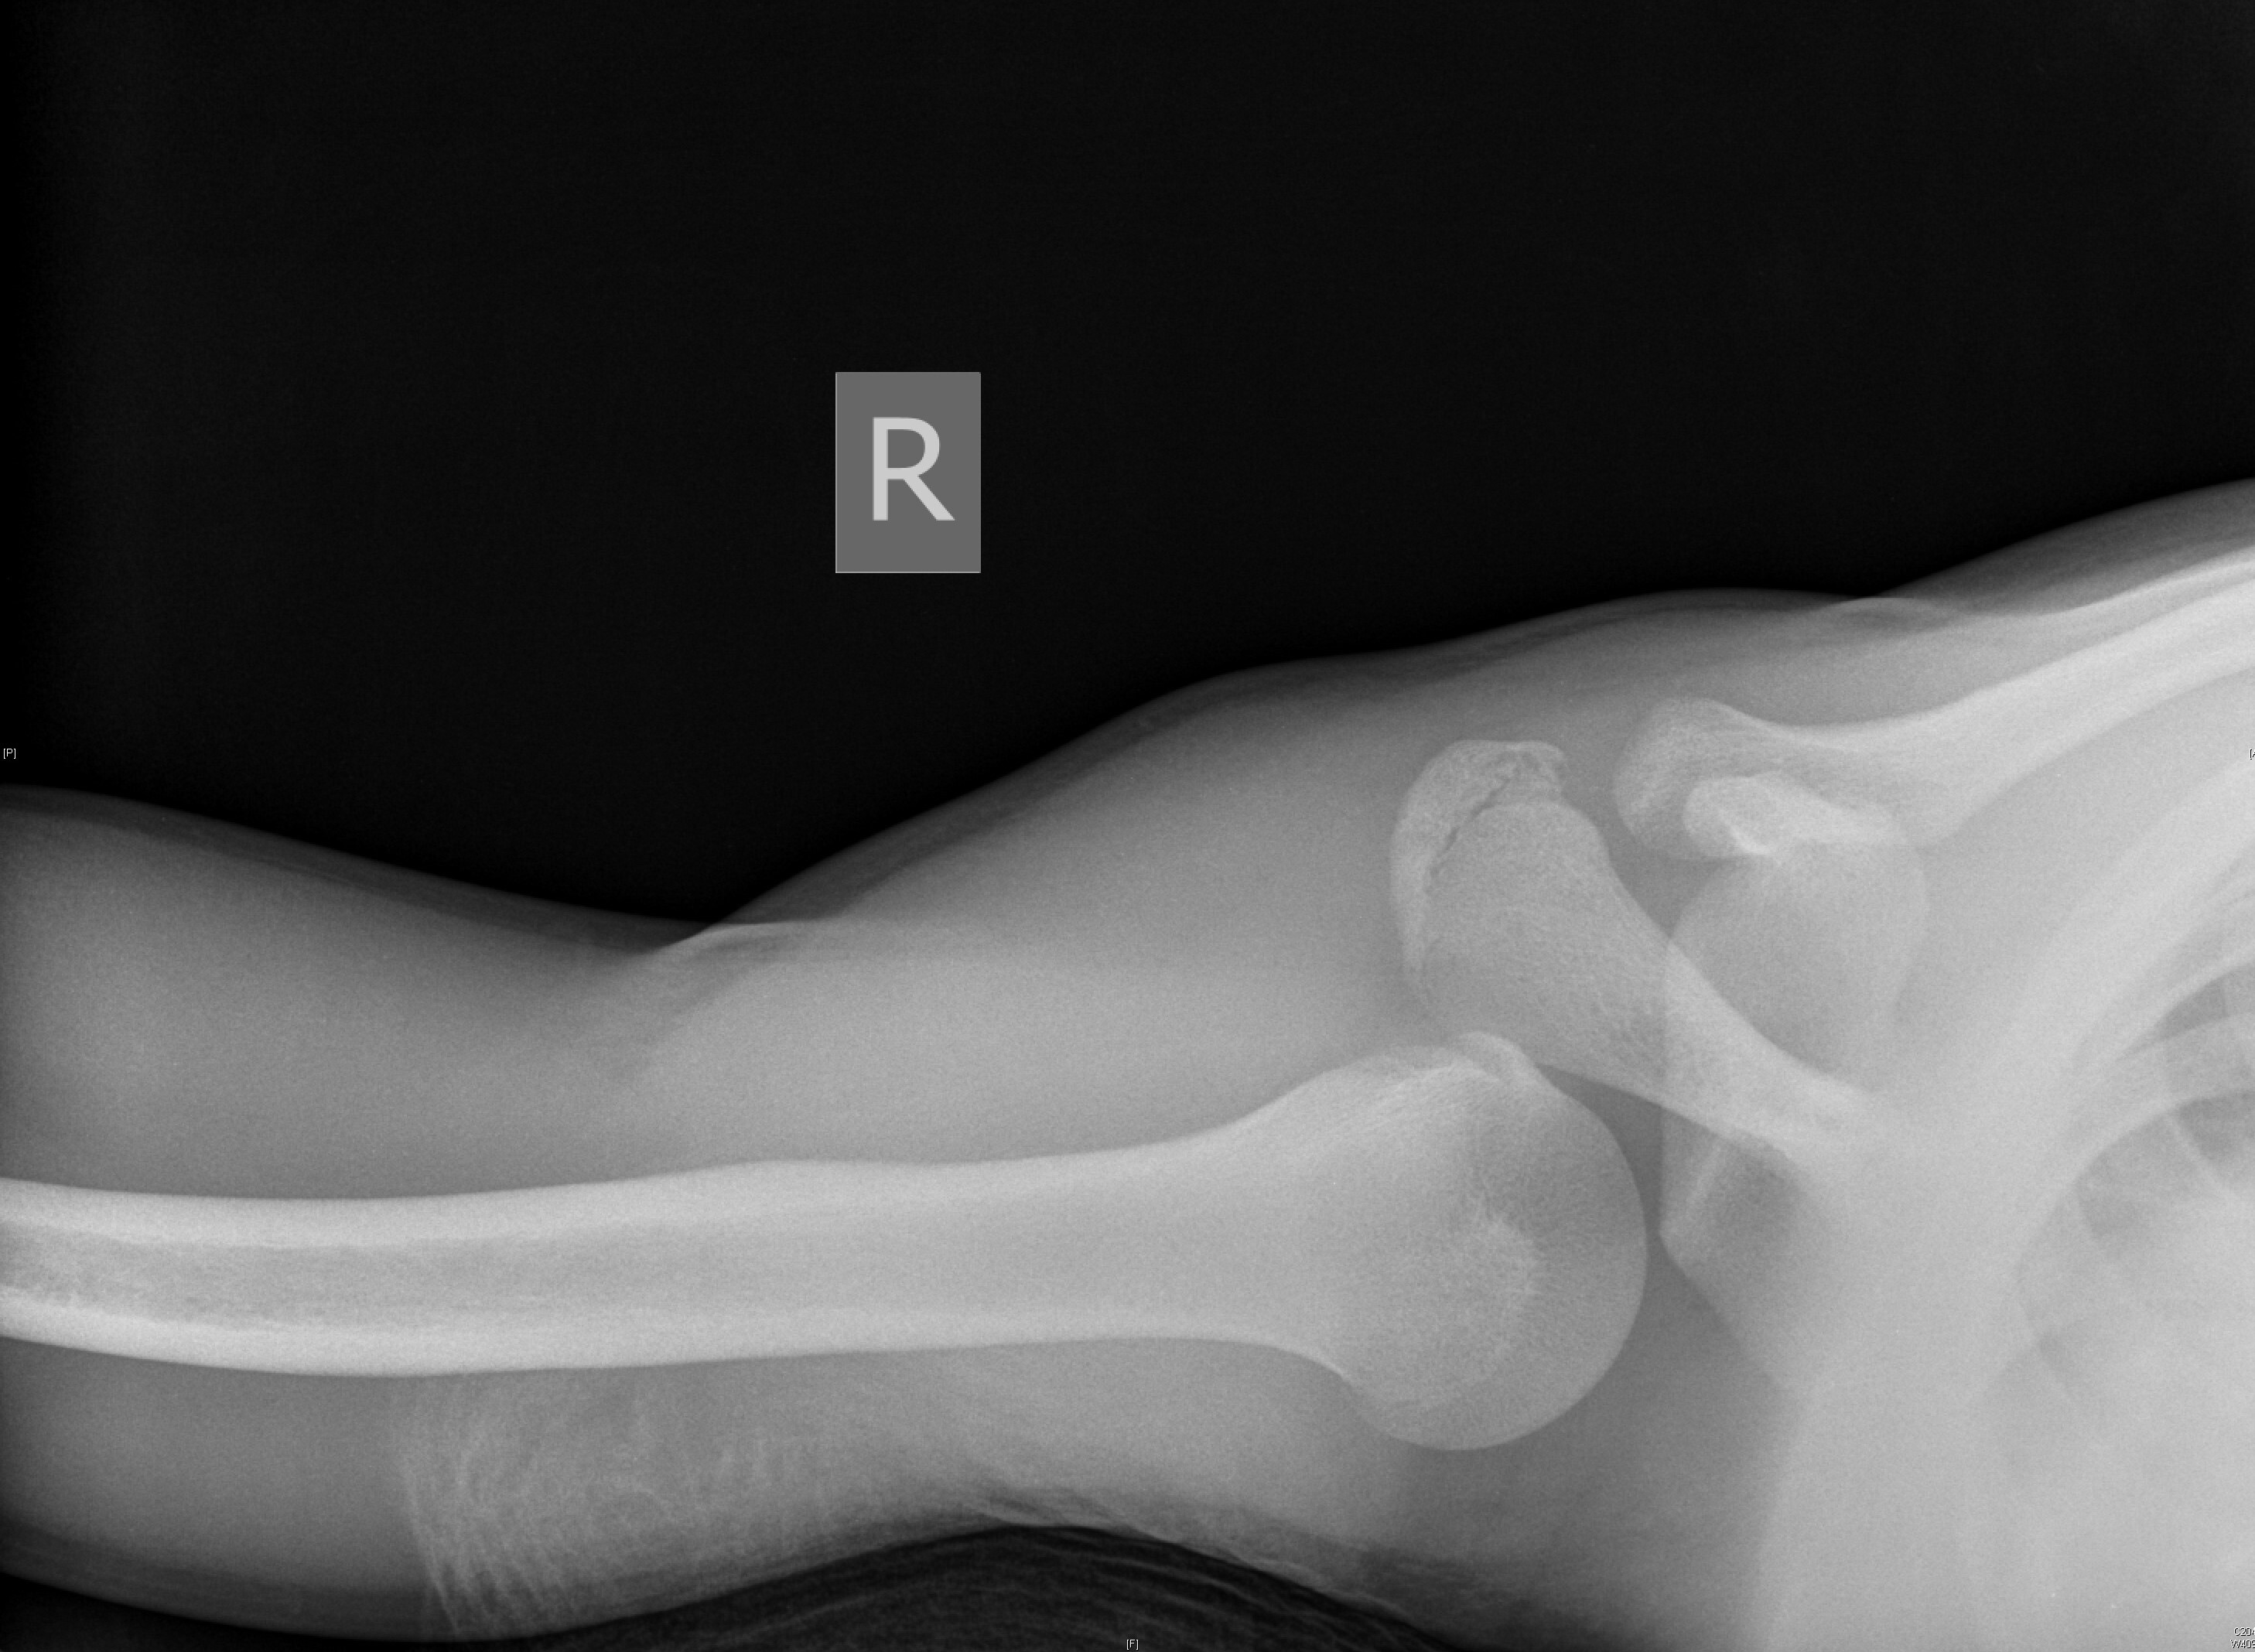

Posterior dislocations are easy to miss because the arm is in internal rotation and adduction. On AP radiograph, the posteriorly dislocated and internally rotated humeral head creates a “light bulb” sign, which may be noted. Nonetheless, posterior dislocation will be viewed best on the axillary view. (See Figures 3 and 4.) Posterior dislocations are at higher risk of surgical neck fracture, reverse Hill-Sachs lesions, and rotator cuff injuries.47,48

Figure 4. Posterior Dislocation Axillary View |

![]() |

Source: Used with permission from J. Stephan Stapczynski, MD. |